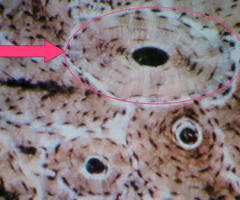

term image

osteon

central canal